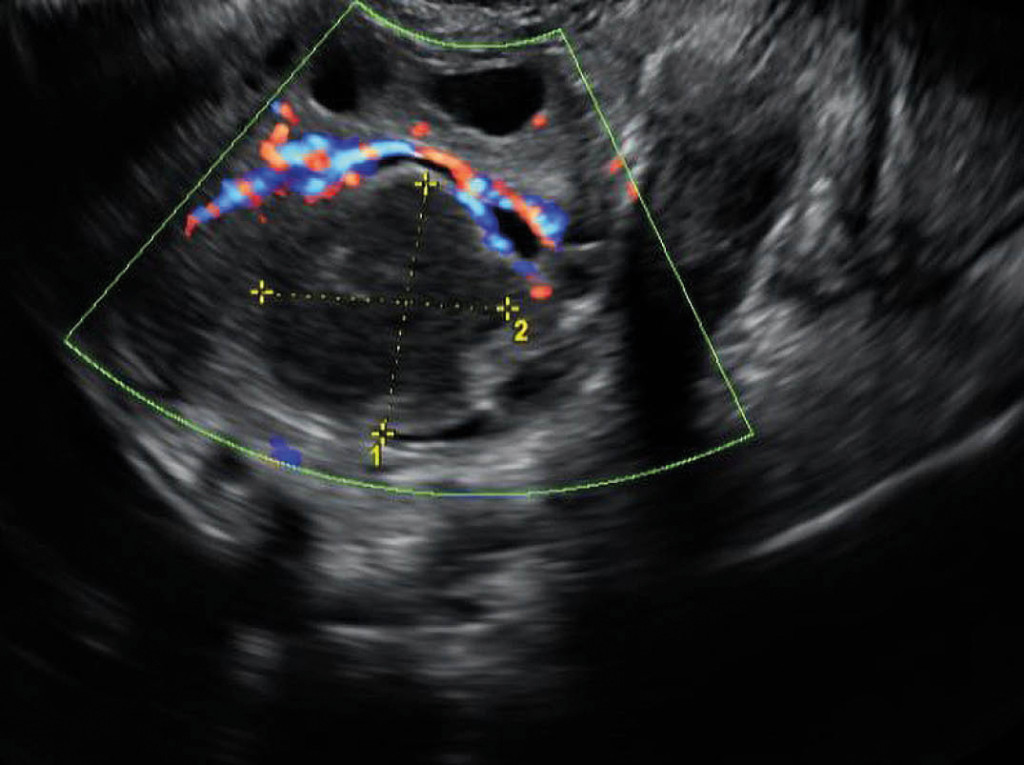

During the gynaecological examination, insertion of a vaginal speculum was clearly painful. The examination revealed abundant yellowish, viscous discharge with no particular odour. Transvaginal ultrasound showed bilateral hypoechoic ovarian masses (Figure 2). Ultrasound-guided transvaginal puncture was performed, yielding moderate amounts of pus. This was cultured for gonococci and mycobacteria in addition to standard aerobic and anaerobic flora. The specimen material was sent for testing on a flocked swab (eSwab). Cervical and vaginal secretions were tested for Chlamydia trachomatis and Neisseria gonorrhoeae using PCR. In consultation with an infectious diseases specialist, the patient's antibiotics were changed to ceftriaxone and metronidazole. This regimen is effective against abdominal abscesses as well as gonococci.

Figure 2 Vaginal ultrasound showed an ovarian cyst measuring 2.5 × 2.4 cm, with hypoechoic content.